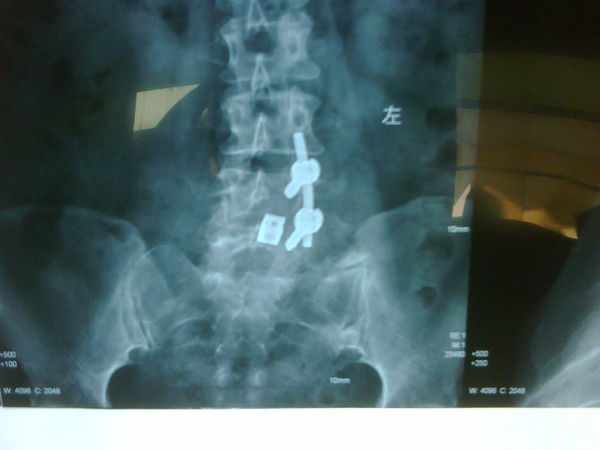

腰椎间盘突出症的手术终极治疗